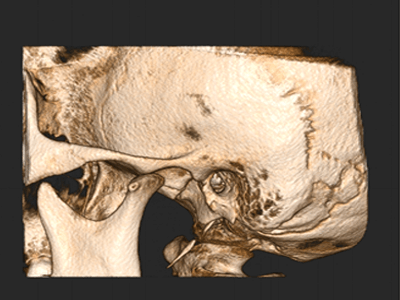

Pro Patient: Our state-of-the-art cone-beam computed tomography (CBCT) technology could selectively image the sinus, oral maxillofacial, para-nasal sinuses, ear & throat regions.

We practice the ALARA principle; (As low as Reasonably Achievable) all scans are restricted to the “Field of View” of your dentist’s prescription. It is taken using (1) pulsed x-ray exposure protocols, (2) real-time-automatic exposure control of the x-ray dose based on the patient’s actual bone density & (3) high resolution digital x-ray image sensors. These factors lead to a significant reduction in x-ray exposure equivalent to only 10% of the x-ray dose of a medical CT-Scan.

The aforementioned technology is inherent in the “myRay X9 CBCT Scan” that we use. myRay X9 is an Italian-made Oral Maxillofacial CT-Scan, certified compliant by European, Japan, USA and other international authorities in radiation safety.